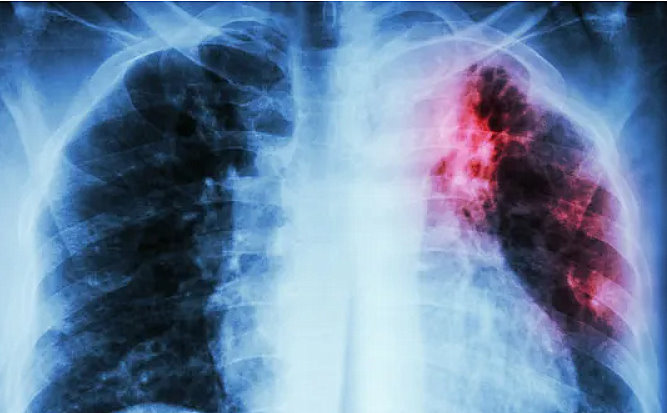

Considerada uma doença infeciosa que afeta principalmente os pulmões, a tuberculose ainda continua fazendo vítimas fatais e novos casos em Marília. A Secretaria Municipal de Saúde de Marília emitiu uma nota oficial confirmando o 5º óbito. Desde o começo do ano a cidade registrou 47 casos confirmados, contra 63 durante 2023 e seis mortes.

A infecção pulmonar causada pela tuberculose tem como principais sintomas febre, tosse, expetoração, perda de peso, fadiga, dor no peito entre outros sintomas.

É provocada por uma bactéria (bacilo de Koch) e que pode ser fatal. Para além do sistema respiratório, a tuberculose também pode afetar outros órgãos, como olhos (tuberculose ocular) e intestino.

O bacilo de Koch afeta, principalmente, os pulmões.